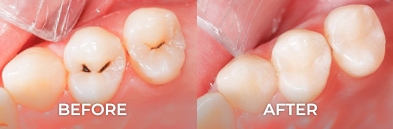

Root Canal Before and After in Mexico

Want to regain confidence in your smile? Our root canal gallery shows you real results: root canal pictures before and after that tell stories of transformation. Leave the pain and worry behind, and welcome a radiant, healthy smile. With our team of endodontic experts, each case is approached with care and precision, guaranteeing results that will take your breath away.